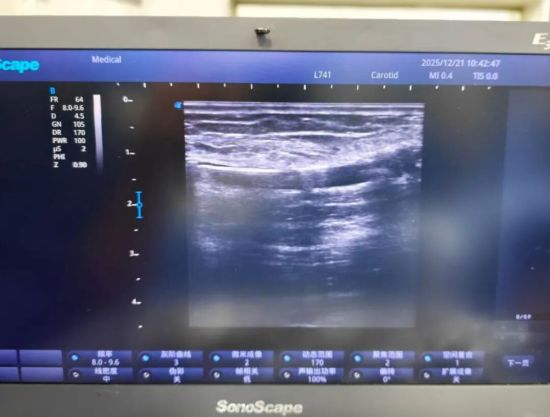

经过充分的术前准备,手术在局部麻醉下进行。肾内科医护团队在超声实时引导下,经皮穿刺建立微小通道,将球囊导管精准送达血管狭窄部位。通过压力泵充盈球囊,轻柔扩张狭窄血管壁,直至血管管径恢复正常,手术顺利完成。超声引导下动静脉造瘘后球囊扩张术(PTA)的过程创伤小,仅留下穿刺点痕迹,且出血少、痛苦轻,时间短、安全性高。术后患者无需卧床静养,很快便可正常活动,次日即可顺利进行血液透析。

超声引导下动静脉造瘘后球囊扩张